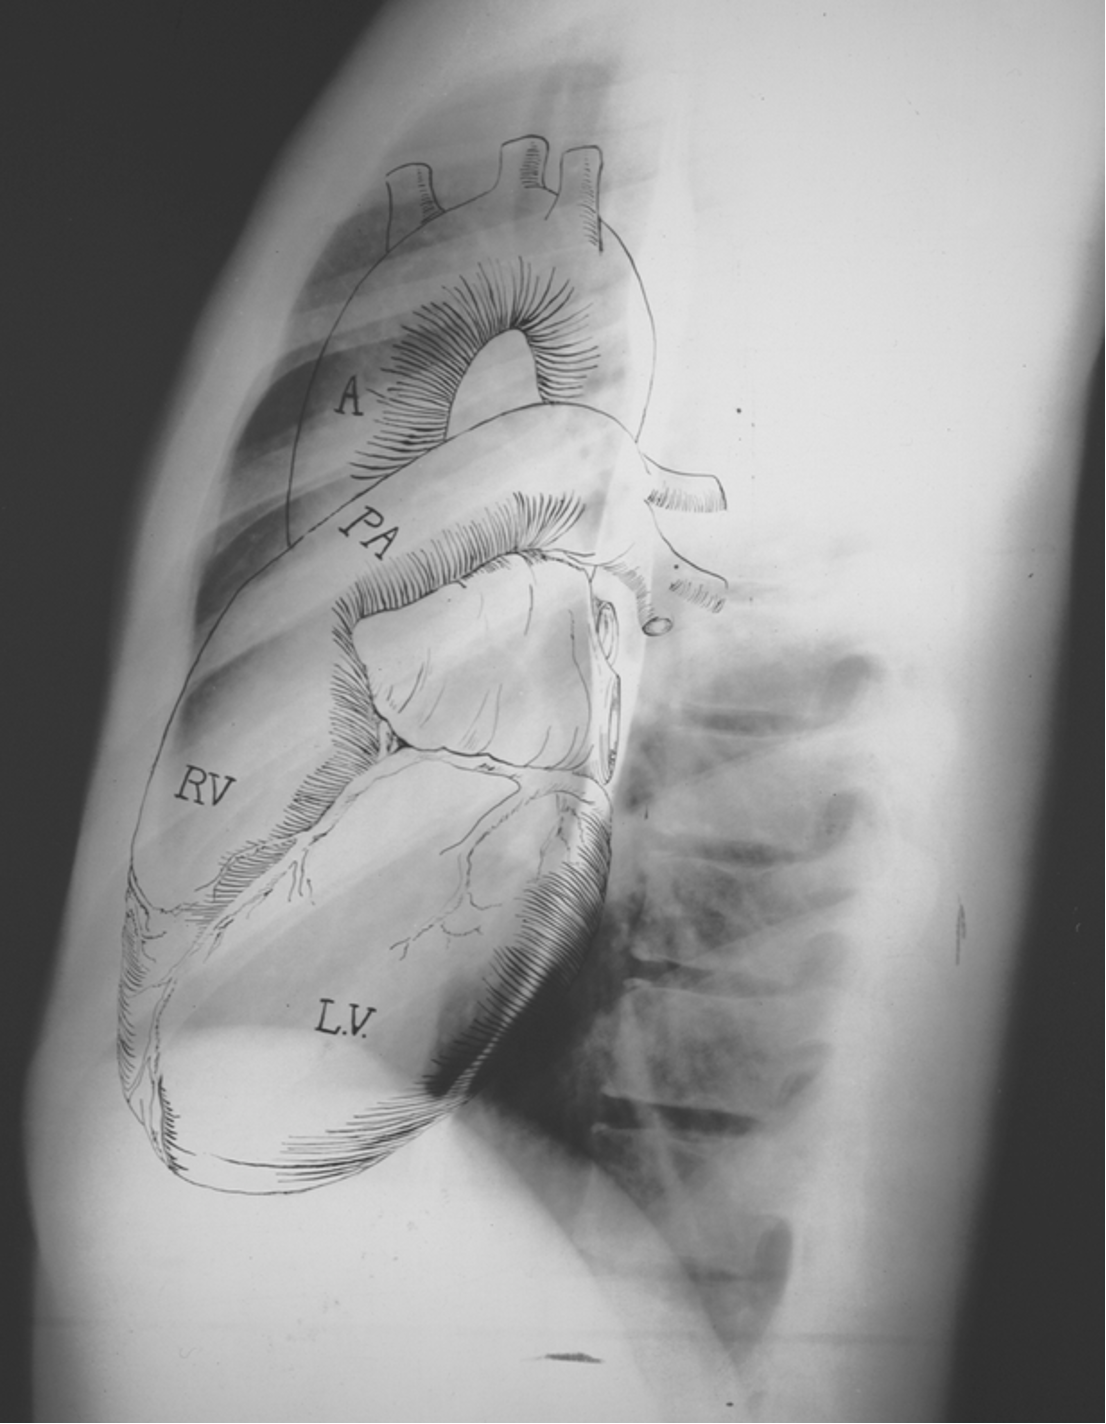

Normal CXR (PA & Lateral)

Name the structures according to letter

A – Trachea

B – Clavicle

C – Right Atrium

D – Diaphragm

E – Cardiophrenic angle (Costocardio)

F – Left upper lobe

G – Gastric Bubble

H – Left Hilum